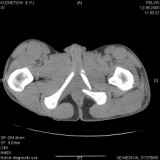

Уважаемые коллеги! Хотелось бы услышать совет по тактике лечения представлленого больного.Поступил после лечения в одном изотделений области. Травма 2,5 месяца назад. После выведенияиз шока был произведен остеосинтез перелома бедра, предплечья, до перевода к нам проводилосьвытяжение по оси шейки бедра за стержень, введенный в большой вертел. На сегодня деформацияригидна, клинически мобильности не определяется. Заранее признателен. P.S. Данный вид травм не включен в перечень "высокотехнологичных операций", направить длялечения по квотам Минздрава очень сложно.

Привет, Леонид. Оскольчатый высокий двухколонный перелом в такие сроки трогать не надо, т.к. это про такие переломы сказано: "кто с ножом на Ж. пойдет тот в ней и останется...".

Если заболит после начала нагрузки в 4-6 месяцев - эндопротез.